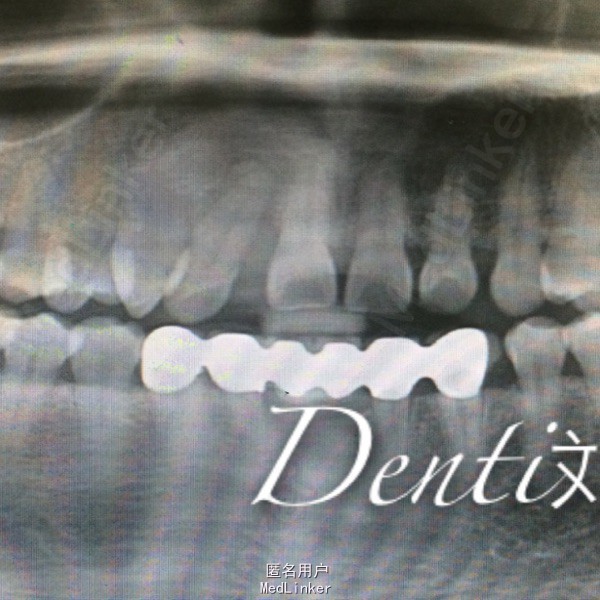

专科检查:口腔卫生一般,前牙扇形打开,散在间隙,开 牙合 ,右上2牙体完整,远中颊侧移位,松动I度,牙龈退缩4—6mm,未探及深牙周袋 辅助检查:X线片示,右上2牙槽骨退缩至根尖1/3,根管恰充填

诊断:牙周炎 处置:右上树脂充填,改形修复